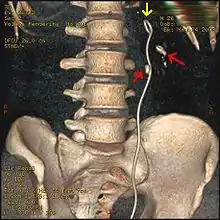

وقد أصبح تنظير الحالب ذا شعبية متزايدة بعدما أصبح منظار الحالب ذو الألياف البصرية المرن، والصلب أصغر حجمًا. وتتضمن تقنية تنظير الحالب وضع دعامة (أنبوب صغير يمتد من المثانة حتى الحالب، وفي الكلى)؛ لتوفير الإغاثة الفورية للكلى المتضررة. يمكن أن يكون وضع الدعامة مفيدًا لإنقاذ الكلى المعرضة لخطر الفشل الكلوي الحاد نتيجة سبب بعد الكلى، مثل زيادة الضغط الهيدروستاتيكي، والتورم، والعدوى (التهاب الحويضة والكلية، وتقيح الكلية) بسبب عرقلة الحصوة لمجرى البول. وتتراوح الدعامات الحالبية في الطول من 24 إلى 30 سم (9.4 إلى 11.8 بوصة)، ومعظمها لها شكل يشار إليه عادة باسم "مزدوج J" أو "ضفيرة مزدوجة"، بسبب وجود حلقة في كلا الطرفين. وهي مصممة للسماح للبول بالتدفق قبل الجزء المسدود في الحالب. ويمكن الاحتفاظ بها في الحالب لعدة أيام إلى أسابيع حتى يتم علاج العدوى، وتفتيت الحصوة بواسطة الموجات الصادمة أو عن طريق طرق العلاج الأخرى. توسع الدعامات الحالبية، مما يسهل إدخال الآلات، كما توفر أيضًا معلمًا واضحًا للمساعدة في تصور الحالب وأي حصوات مرتبطة به في الفحص الشعاعي. وقد يسبب وجود دعامات الحالب في الداخل بعض الانزعاج، وعدم الراحة للمريض، وتواتر أو إلحاح البول، والعدوى، ويتم الشفاء من ذلك بشكل عام بعد إزالة الحصوات. يمكن إزالة معظم دعامات الحالب بمنظارالمثانة تحت التخدير الموضعي بعد حل التحصي البولي.[95]